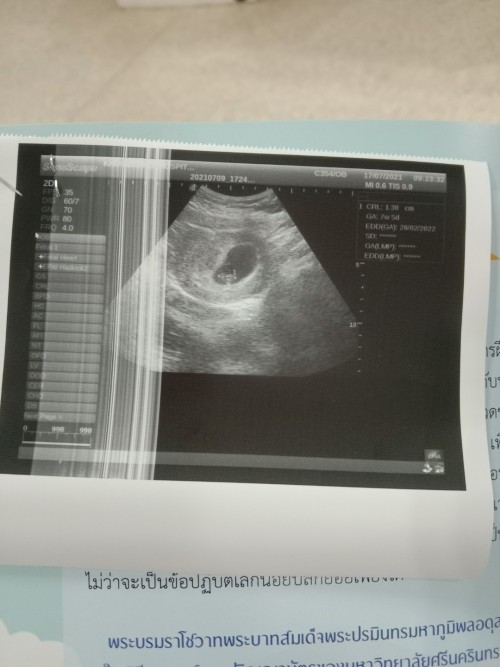

วันนี้ได้เข้าไปอัลตร้าซาวกับหมอสูติได้พบว่ามีถุงตั้งครรภ์แต่ไม่มีตัวอ่อน ถ้านับอายุครรภ์จากปจด.คือ10w.แต่คุณหมอบวกลบท้องลม คุณแม่นัดอีก2อาทิตย์ถ้าไม่เจอตัวอ่อนก็เปนท้องลม หมอบอกอายุครรภ์อาจจะพึ่งได้7w ใครเจอแบบนี้บ้างมั้ยค่ะ เครียดยุค่ะ